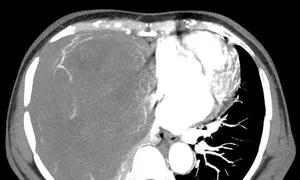

Hình ảnh khối u choán hết khoang lồng ngực của bệnh nhân. Ảnh: Bệnh viện cung cấp

Bệnh nhân cho biết lý do không phẫu thuật khi ấy bởi u nhỏ không gây khó chịu. Gần đây bà khó thở, sức khỏe giảm sút, sụt 5 kg. Bác sĩ Bệnh viện Ung bướu Hà Nội khám ghi nhận lồng ngực phải bệnh nhân có khối đặc kích thước 20x15 cm đè xẹp phổi, thâm nhiễm trung thất, thành ngực. Sinh thiết khối u kết quả giải phẫu bệnh là u xơ đơn độc.

Bác sĩ tiên lượng ca mổ lấy u nhiều khó khăn do bệnh nhân có thể trạng gầy yếu, khối u lớn giàu mạch nuôi chiếm gần hết khoang lồng ngực. Ngày 30/9, TS.BS. Phan Lê Thắng, Trưởng khoa Ngoại Theo yêu cầu, Bệnh viện Ung Bướu Hà Nội, cho biết êkíp phẫu thuật hội chẩn tính toán kỹ phương án mổ, khống chế nguồn mạch máu nuôi để hạn chế mất máu cho bệnh nhân. Khối u được bóc tách thành công, nặng hơn 2 kg.